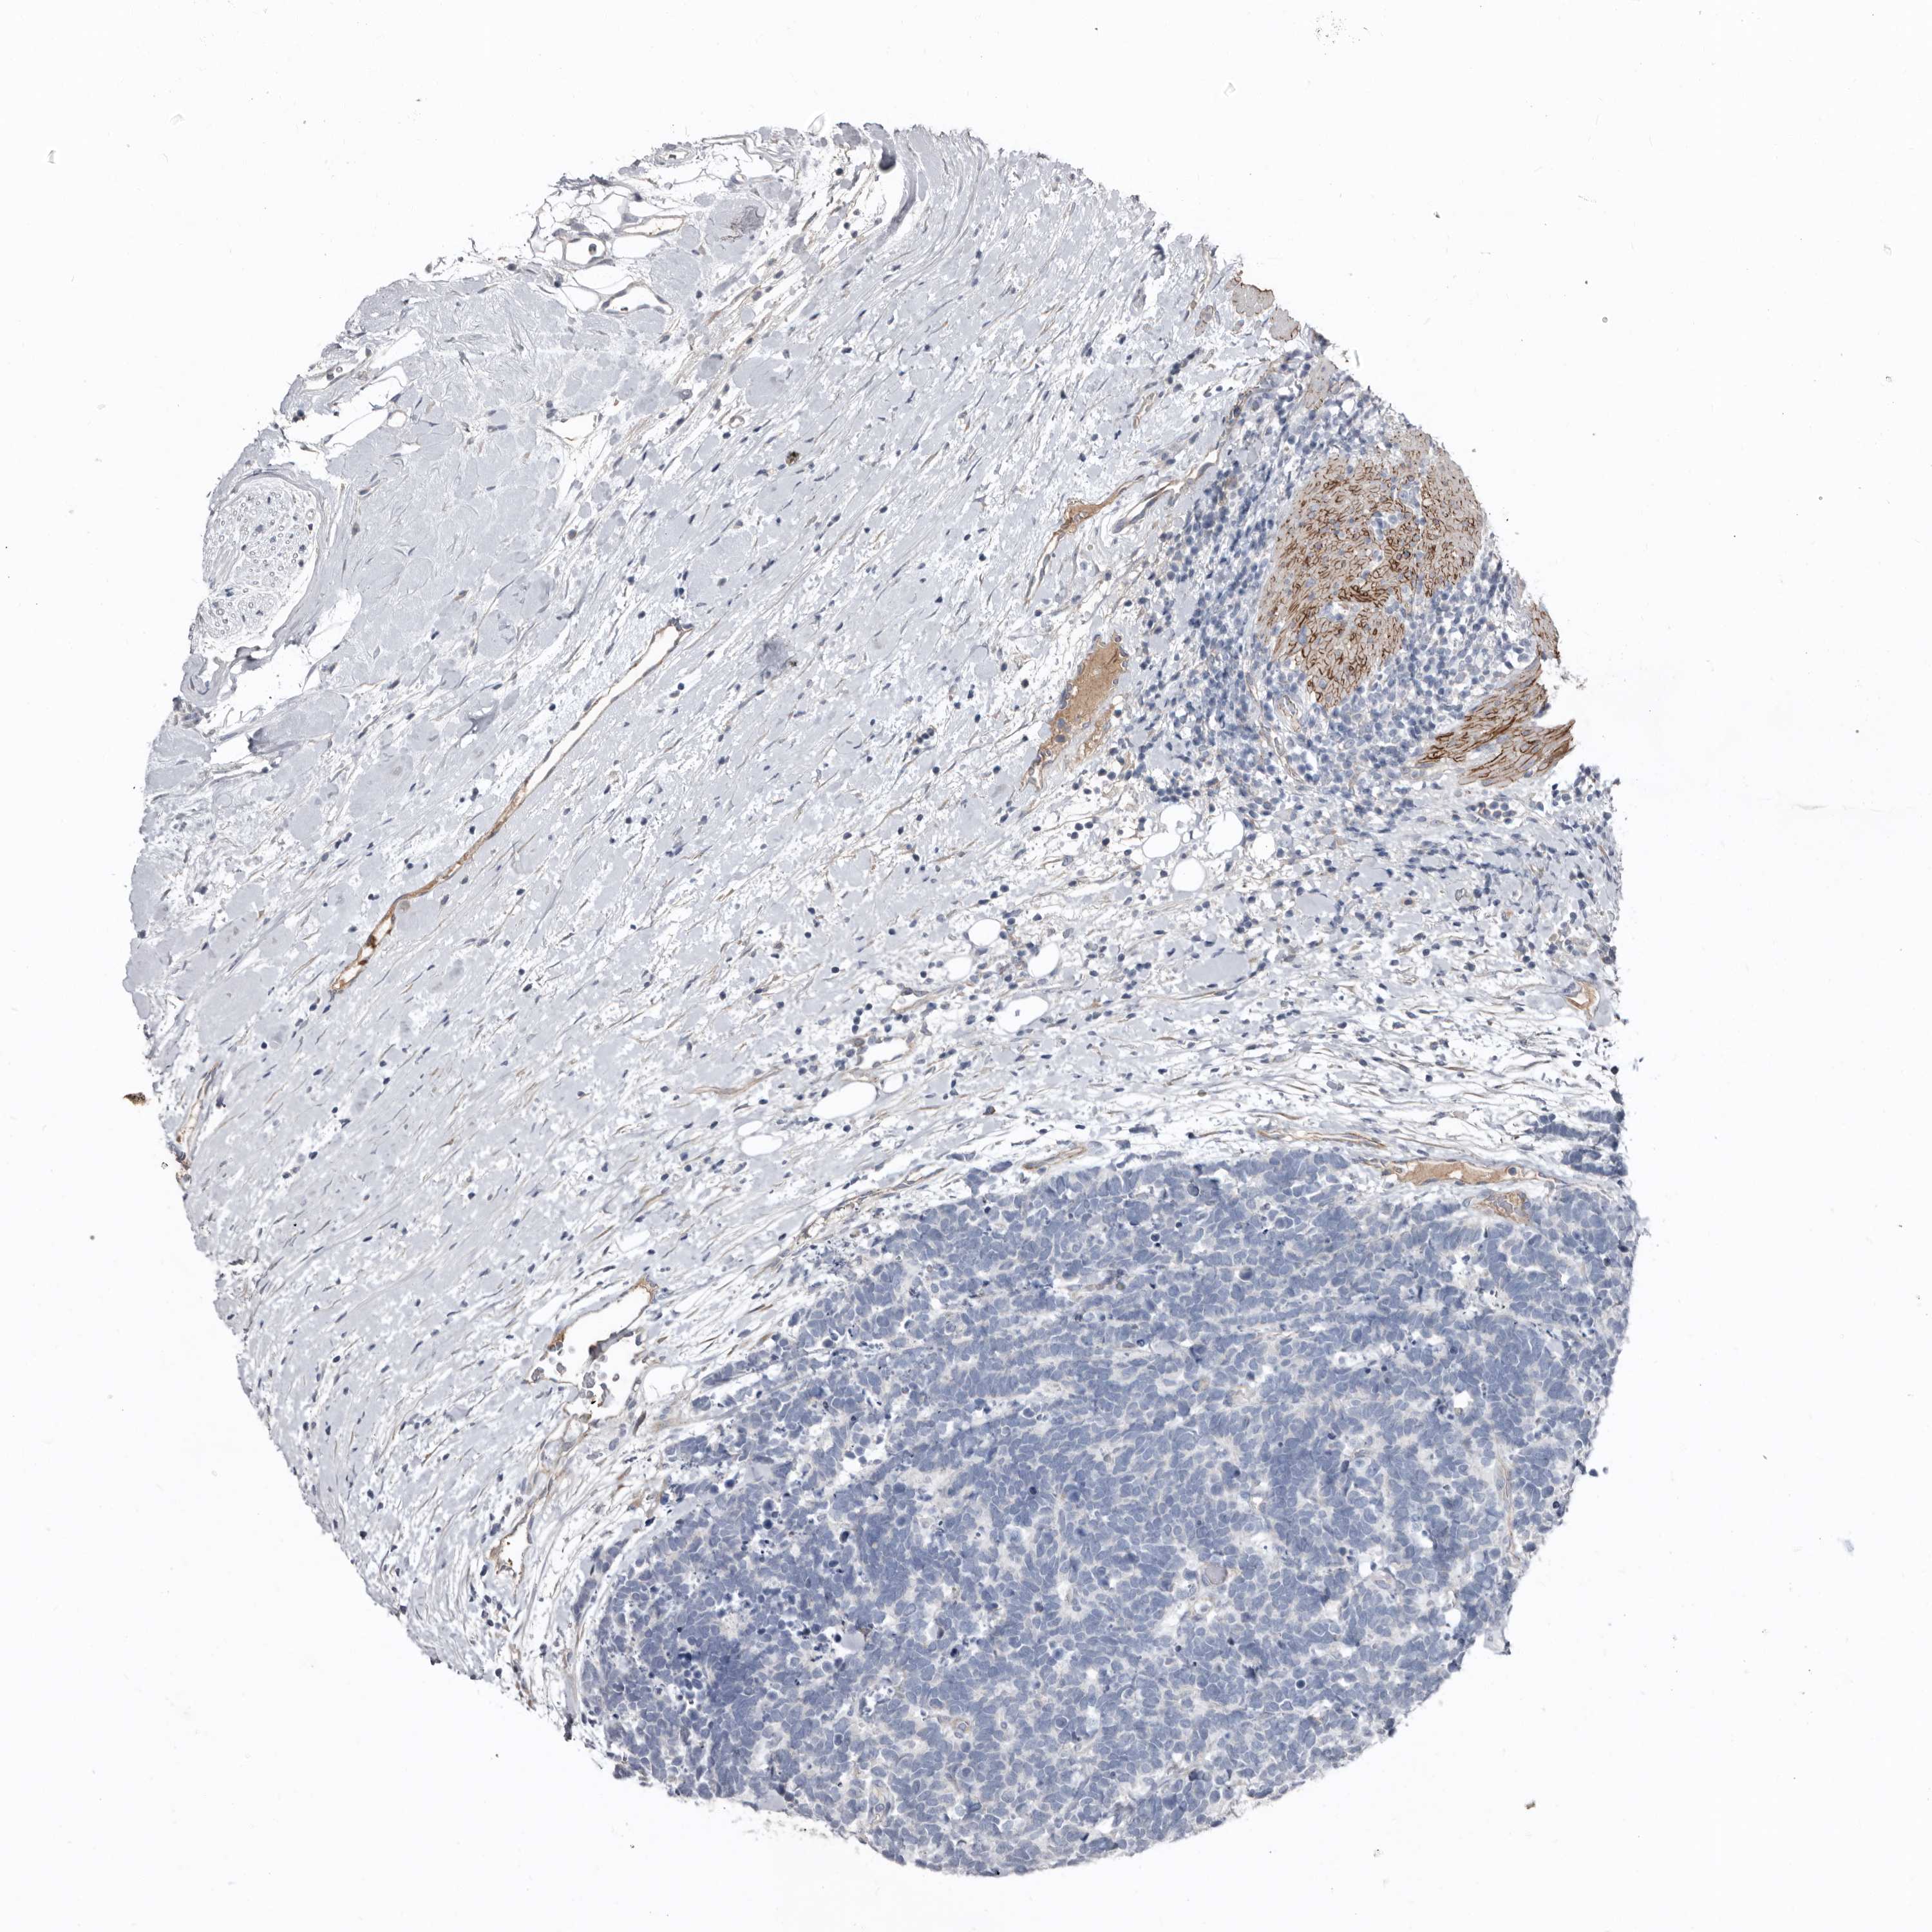

CARCINOID - Protein expressioni

A mouse-over function shows sample information and annotation data. Click on an image to view it in a full screen mode. Samples can be filtered based on level of antibody staining by selecting one or several of the following categories: high, medium, low and not detected. The assay and annotation is described here.

Antibody stainingi

Antibody staining in the annotated cell types in the current human tissue is reported as not detected, low, medium, or high, based on conventional immunohistochemistry profiling in selected tissues. This score is based on the combination of the staining intensity and fraction of stained cells.

Each image is clickable and will lead to virtual microscopy that enables deeper exploration of all samples and also displays staining intensity scores, fraction scores and subcellular localization as well as patient and tissue information for each sample.

Antibody HPA025019

Antibody HPA029553

Carcinoid, malignant, NOS

Carcinoma, NOS